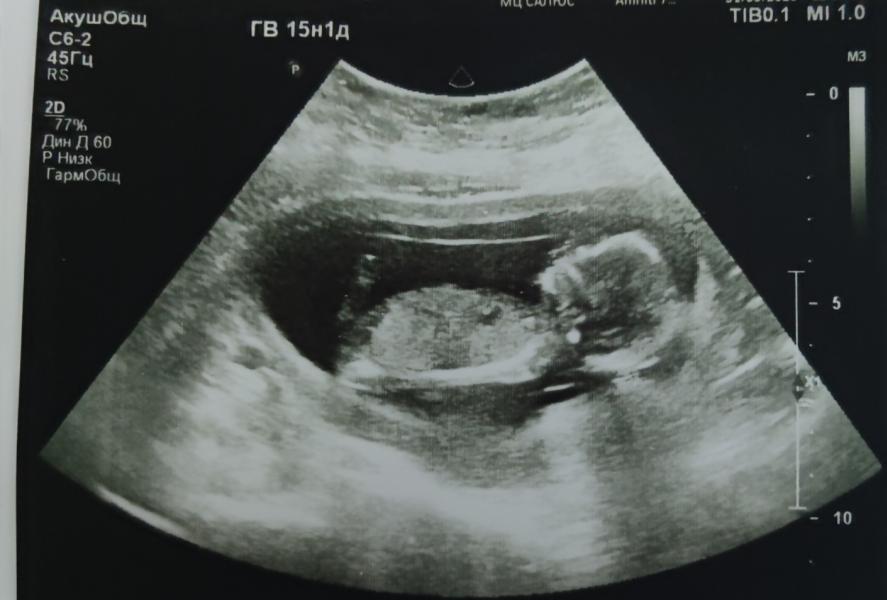

Девочки делаем ставки кто? ☺

Ну вот ждём в 18 недель вроде уже должно видно быть хорошо говорят

Не знаю правда или нет, но говорят если ребёнок лежит прям горизонтально то будет мальчик, а если чуть вертикальнее то девочка.. не помню где я это слышала🤦♀️меня сейчас тапками закидают🙊но я вам тоже желаю чтобы у вас была девочка...